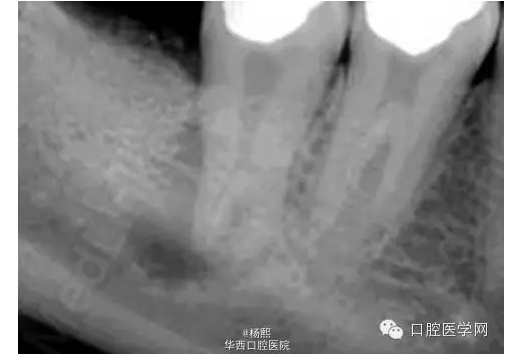

X線片示46、47牙合面牙體組織高密度影像,47牙輕度牙發(fā)育異常,髓室底較低,根尖周組織可見暗影。

討論:此病例屬于牙發(fā)育異常中的牛牙癥,為重度牛牙癥。牛牙癥(Taurodontism)是指牙髓頂至髓底的高度高于正常,而釉質(zhì)牙骨質(zhì)界的水平?jīng)]有改變、造成髓室向根尖延伸超過牙頸部,根分叉靠近根尖,牛牙癥 根據(jù)髓底向根尖方向位移的程度分為輕度、中度和重度。

(3)X線片表現(xiàn):牛牙癥的異常特征的最直觀表現(xiàn)是在X線片上?;佳莱榉叫投皇窍蜓兰獠烤酆峡s窄的錐形。髓腔極大,髓室的根?向距離遠(yuǎn)大于正常。另外,牙髓腔在牙頸部沒有正常的縮窄,牙根極短。根分歧可能位于距牙根尖之上僅幾個毫米處。Shaw變異的程度,分類為輕度(hypotaurodont)、中度(mesotaurodont)和重度牛牙癥(hypertaurodont)。重度牛牙癥形態(tài)變異最大,牙齒根分歧位置接近牙根尖部,而輕度牛牙癥的變異最輕。